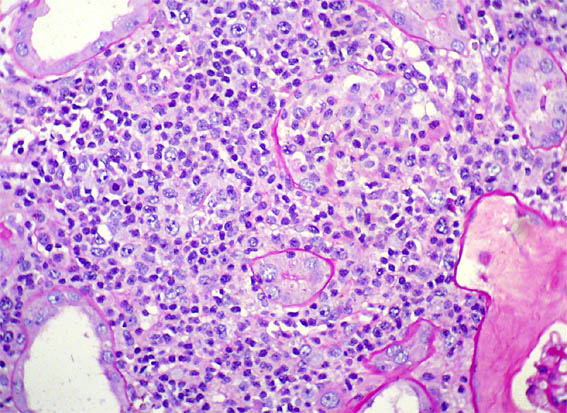

Figure 1. H&E, X40.

Figure 2.